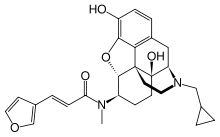

Oripavine derivatives

- Buprenorphine

Structures

| Oripavine derivatives | ||||

Buprenorphine Buprenorphine |

Etorphine Etorphine |

Thienorphine Thienorphine |